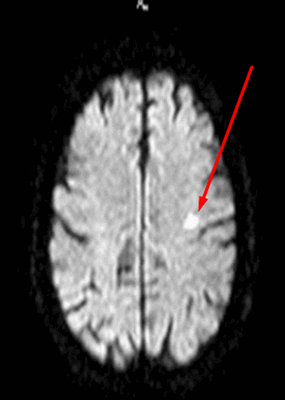

- Раннее выявление возможно при использовании метода переноса намагниченности (ПМ) и диффузионно-взвешенных изображений.

- Стадия 1 (острая): До 4 нед. после повреждения на традиционных МР-изображениях не определяются патологические изменения сигнала.

- Стадия 2 (подострая): Спустя 4-14 нед. на Т2-ВИ визуализируется гипоинтенсивная зона, обусловленная начальным, а не биохимическим распадом миелина и компонентов аксона.

- Стадия 3 (хроническая): Гиперинтенсивная зона на Т2-ВИ (распад жиров и липопротеинов, вазогенный отек, глиоз).

- Стадия 4: Атрофия

Валлеровская дегенерация вследствие инсульта в бассейне средней мозговой артерии в левом полушарии большого мозга. Р1_А1К-изображения (а, b) и Т2-ВИ в аксиальной плоскости (с). В зоне, кровоснабжаемой левой средней мозговой артерией, визуализируется кистозный дефект с глиозом (а). Определяется повышенная интенсивность сигнала от пирамидного пути в левой ножке мозга (b) и в продолговатом мозге слева (с).